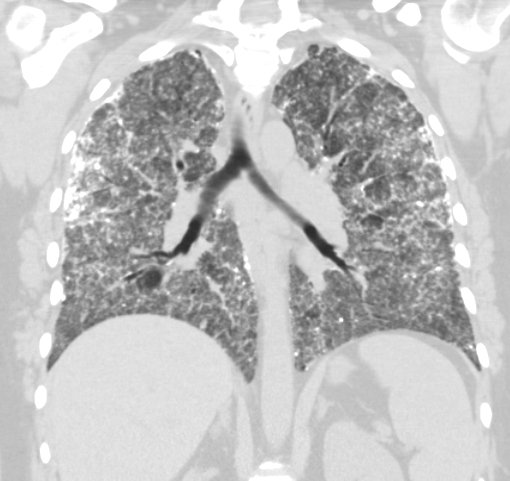

Figure 2: Coronal view of high-resolution chest CT showing extensive bilateral parenchymal calcifications, focal areas of mild emphysematous changes predominantly in the upper lobes, and mild mediastinal and hilar adenopathy.